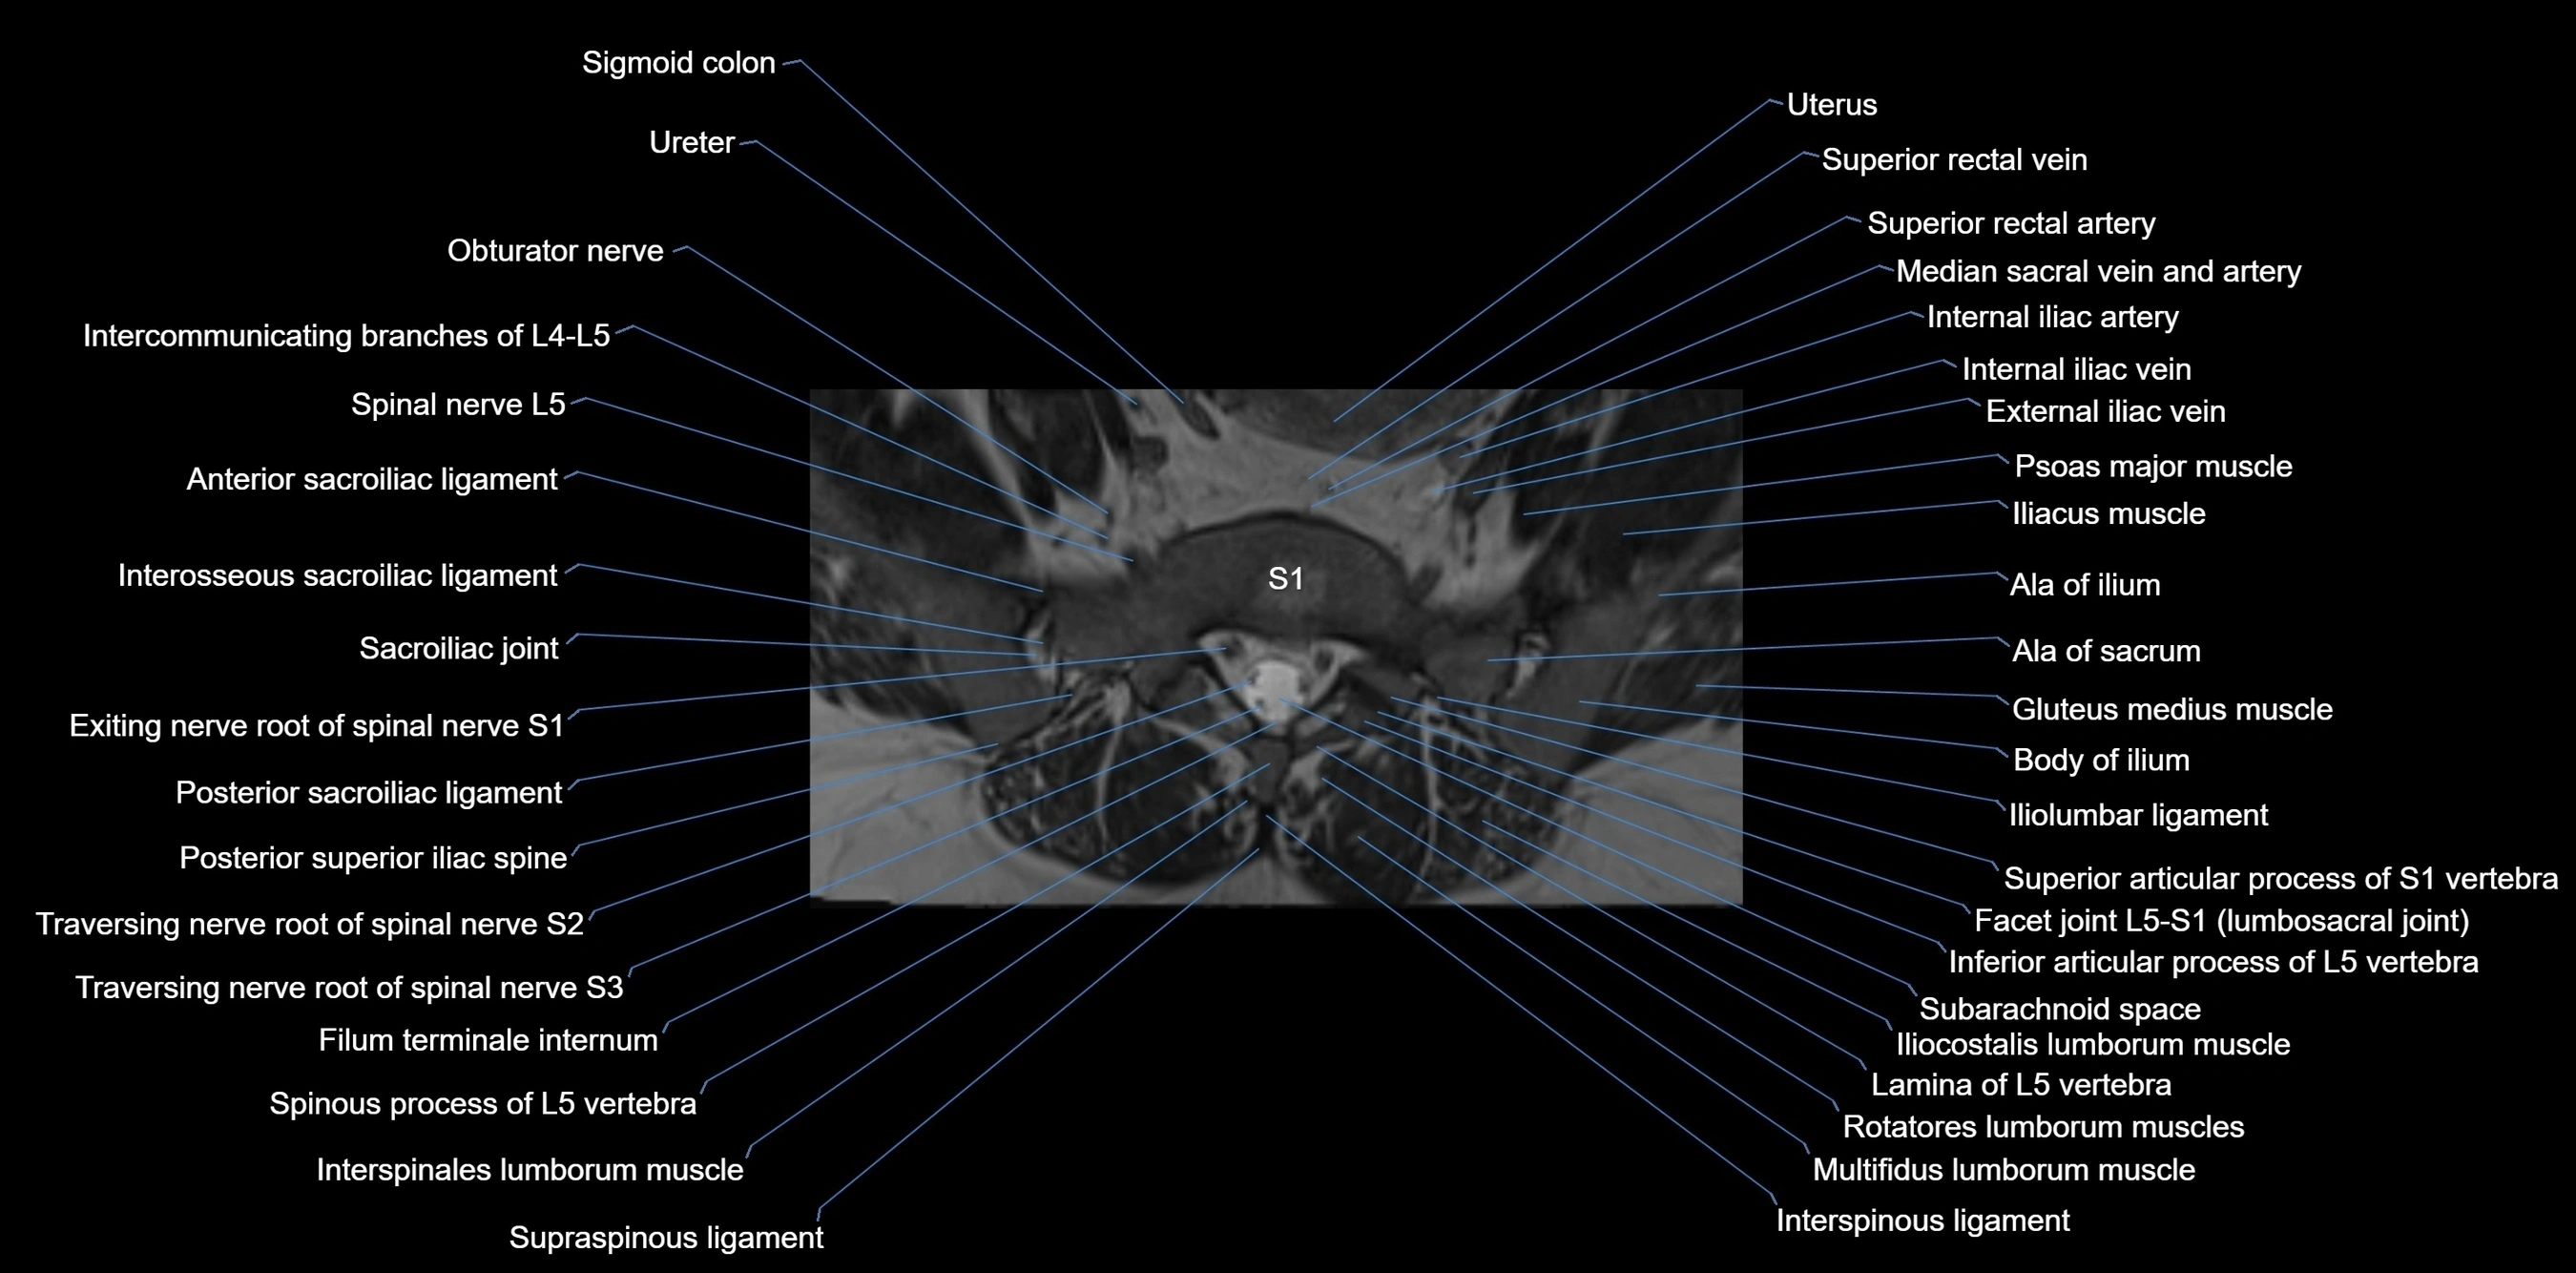

CT image

image